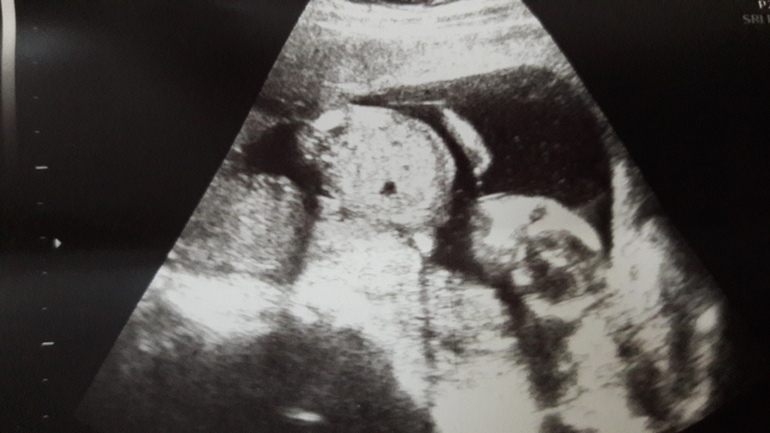

Пол малышаПо м. вчера у меня было 15+4...Шла к уже проверенной УЗИ стке.... Легла в общем, всё хорошо! Всё на месте и всё со мною!!!! Сердечко бьётся, лялечка на месте))))

Прикреплены по задней с тенке, с плацентой всё гуд! 135грамм моя кровинка. Ножки, ручки, головка, сердечко....

Повернула экран и показывала мне мою дочь. Она там брыкалась, отвернулась)))) Так смешно следить за ними... И так быстро забывается увиденное!!!!! Самое главное, что девочка растёт) Это так приятно осозновать!!!!! Мууууурррр!!!!!! ![]()

Ножки.... И потом показала писечку... Доченькино зернышко!!!